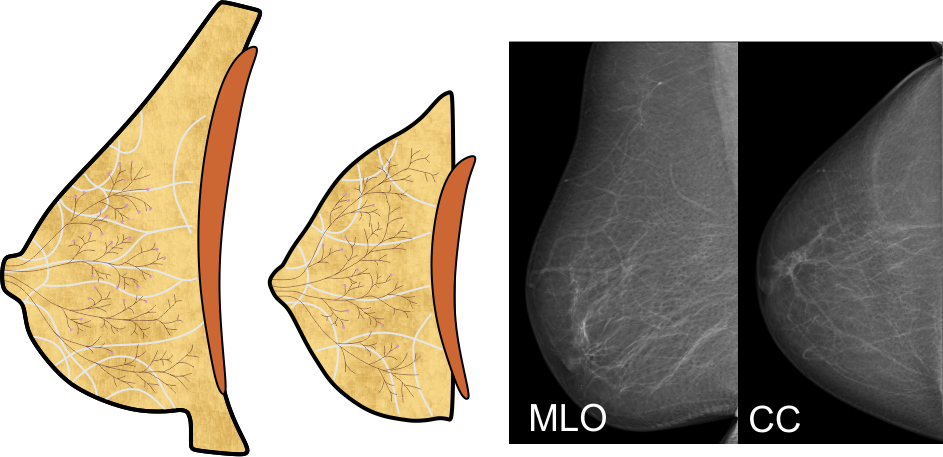

Aufbau der Brust

Die vier oben genannten Gewebearten sind in ihren Anteilen in jeder Brust individuell angelegt. Die meisten Frauen haben eine ausgewogene Verteilung, bei manchen kann jedoch eine bestimmte Gewebeart überwiegen. Dazu verändert sich die Brust mit zunehmendem Alter, die Milchgänge und das Bindegewebe werden vor allem nach dem Wechsel dünner, die 'Blätter' des Baums 'verwelken' - die Drüsenläppchen schrumpfen also, und der Fettgewebeanteil wird größer. Üblicherweise entwickeln sich diese Veränderungen von innen nach außen, und von unten nach oben.

Tumore können aus allen vier Gewebearten hervorgehen. Tumore des Binde- und Fettgewebes sind zumeist gutartig, Tumore der Milchgänge und Drüsenläppchen sind meist bösartig. Diese Tumore werden üblicherweise als Brustkrebs bezeichnet.